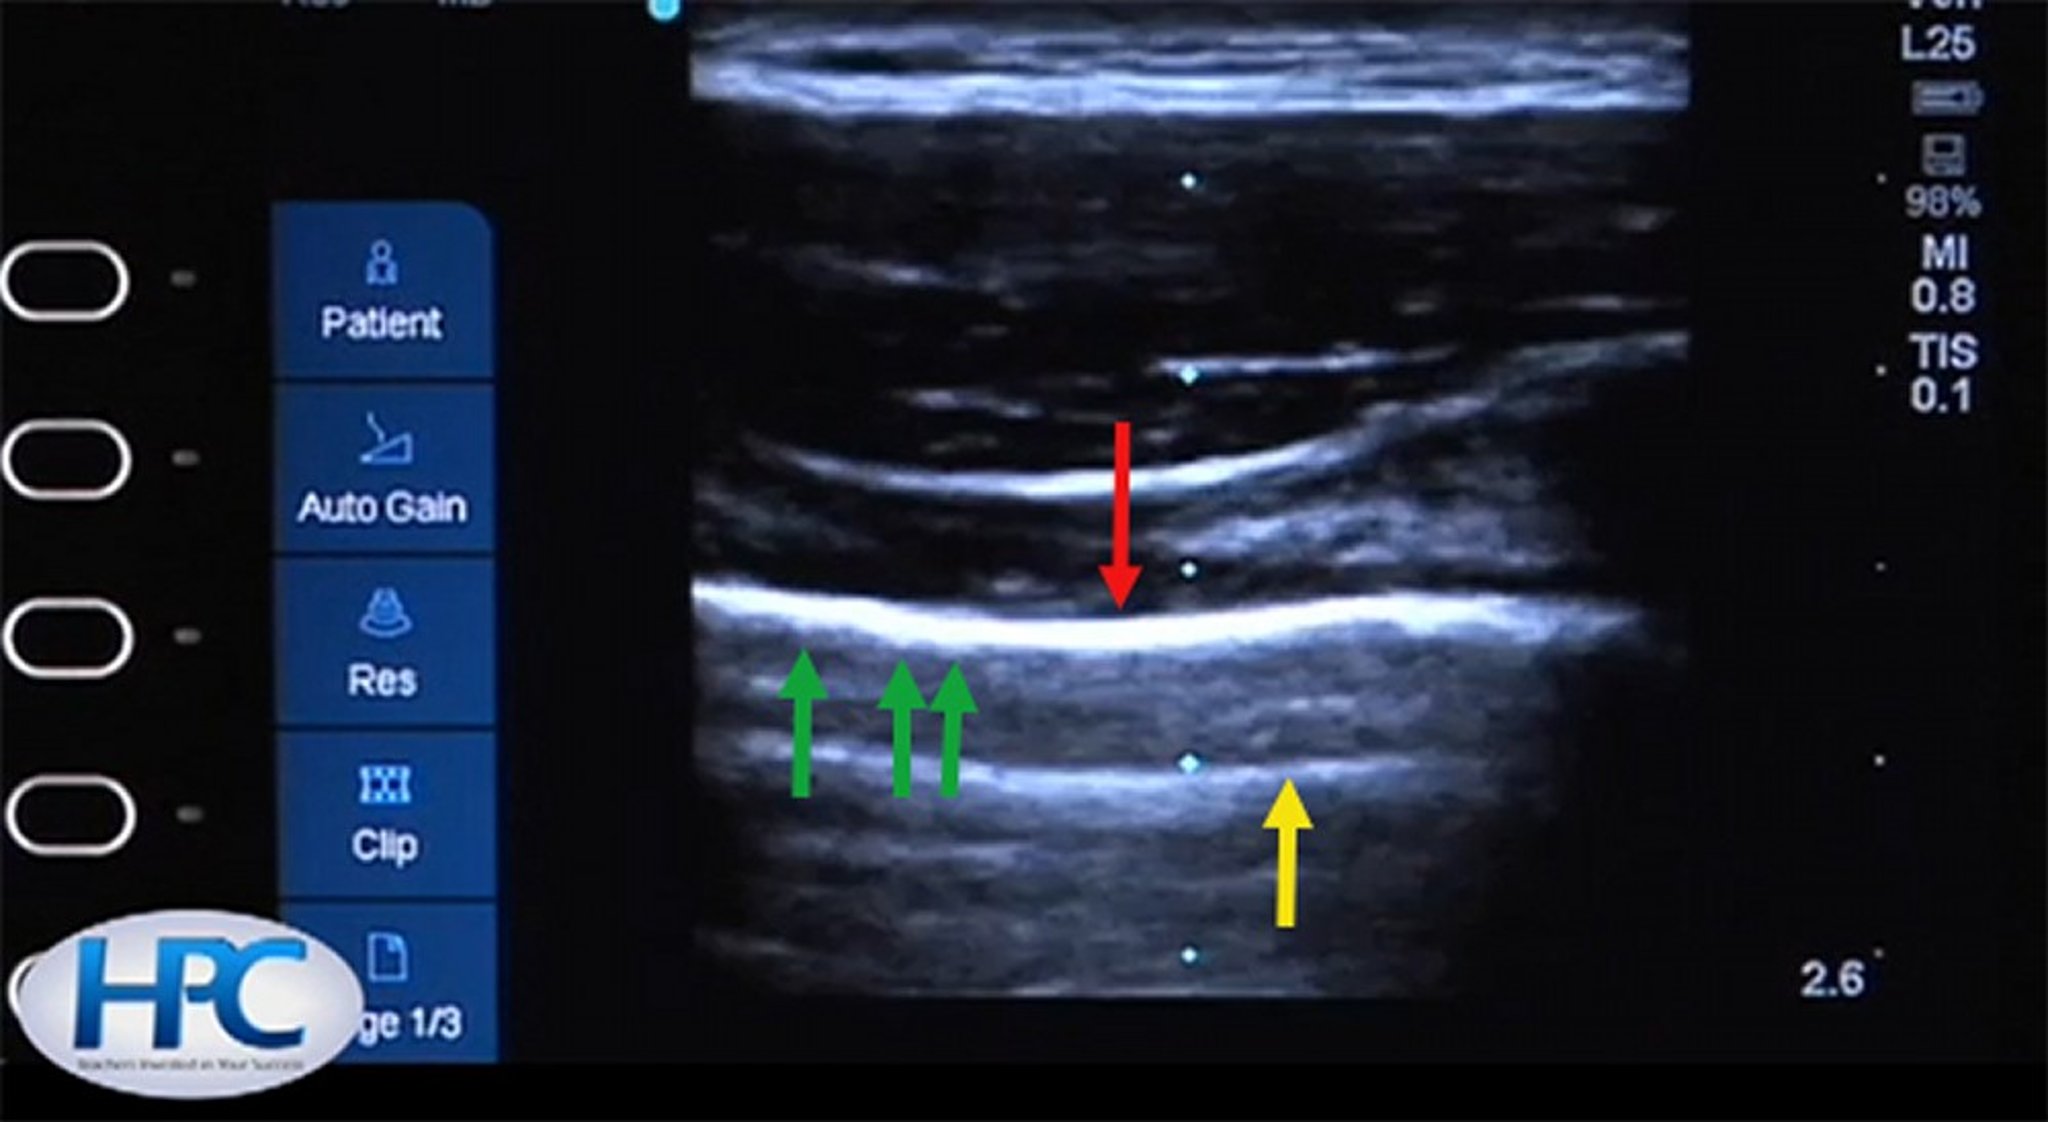

Normal Pleural Line

The pleural line is hyperechoic (red arrow). During respirations, rib sliding will cause the pleural line to shimmer and create an appearance of walking “ants on a log” when visualized in a real-time video (green arrows). A-lines (yellow arrow) appear because of artifactual reflection of the ultrasound waves.